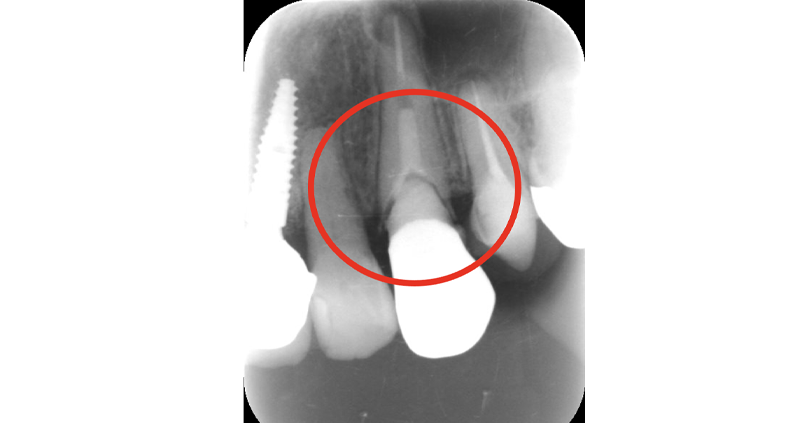

歯が折れている部分

| 写真の説明 | 赤丸:骨のラインより下で歯が折れている部分(通常なら抜歯適応) 青丸:小矯正装置を装着して歯を引っ張り出した状態 黄色丸:引き出した歯にかぶせ物を装着した状態 |